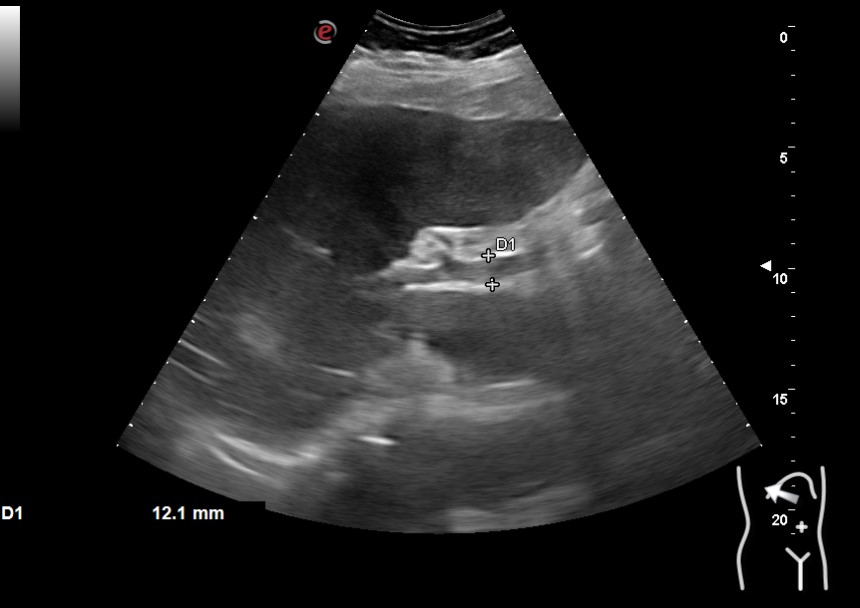

Hallazgos ecográficos

Vesícula biliar desestructurada, de paredes mal definidas con litiasis de 20 mm, que contacta con la pared de la segunda porción duodenal. Porta de tamaño normal. Vía biliar no dilatada.

En los análisis destacaban: GOT 419 GPT 525 FA 373 Bilirrubina 5,3 PCR 184 19.800 leucocitos con neutrofilia. Se realiza tomografía computarizada y nueva ecografía. Se inicia antibioterapia e ingresa con impresión diagnóstica de colecistitis sobre colecsitopatía crónica versus neoplasia vesicular.